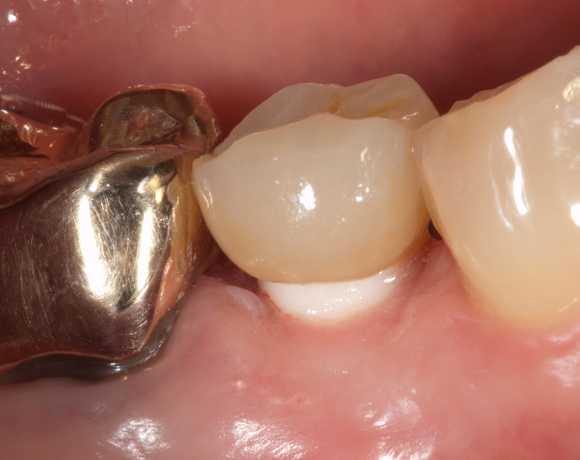

Bei diesem Patientenfall wird die offene Abdrucknahme gezeigt und die Herstellung einer Krone auf einen CAD/CAM Pfosten.